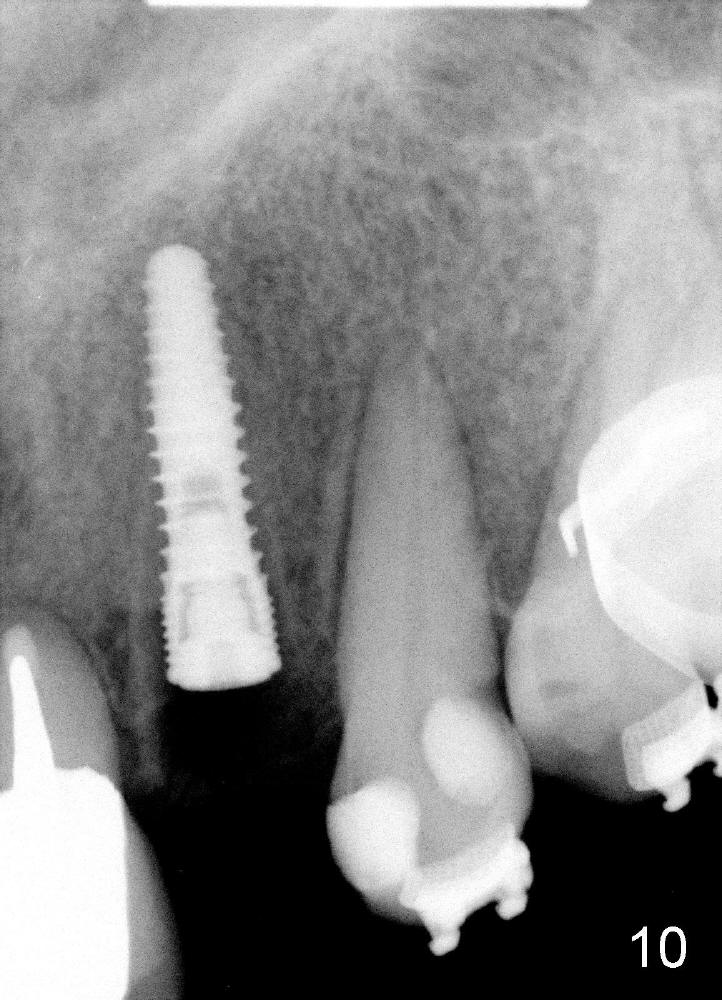

The 2.5 mm reamer is inserted as planned (following the contour of the alveolus (4)). Although the reamer (Fig.7 R) is palatal and there is a gap buccally (*), the handle of the reamer tilts buccally (Fig.8). A straight wall is created by using 2.5 mm reamer (Fig.9). A tapered implant is inserted (3.8x14 mm with apical diameter 2.4 mm, Fig.10). It is supposed to have high torque, but this implant is placed with a knob driver, probably due to osteoporosis. The dilemma is that the patient insists upon immediate provisional. If a tap driver were used, low torque would be found before implantation.